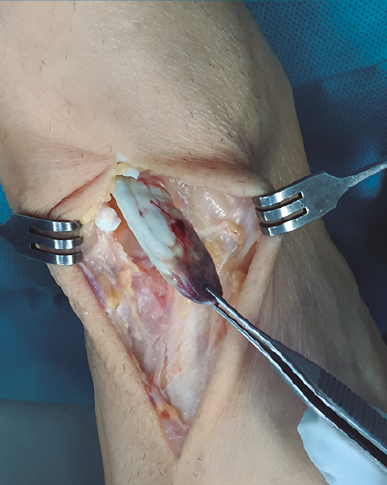

Figura 1. Vaina del tendón tibial anterior con muñón ascendido proximalmente que se transparenta por debajo del retinaculum superior.

Con el paciente en decúbito supino y con isquemia a nivel del muslo, se realiza una incisión cutánea longitudinal anterior al nivel del trayecto del TA, extendiéndola al nivel del mediopié sobre la articulación astrágalo-escafo-cuneana (Figura 1).